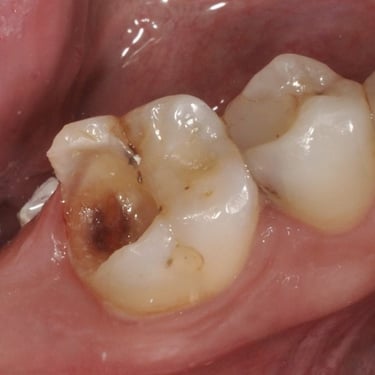

Pulpitis Crónica Hiperplásica

La pulpitis crónica hiperplásica es una inflamación de la pulpa con crecimiento excesivo de tejido pulpar a través de una caries abierta.

Los pacientes notan un tejido rojo que sobresale de la cavidad dental.

El tratamiento incluye la eliminación del tejido afectado y un tratamiento de conducto. Es crucial tratar la caries para evitar infecciones adicionales.